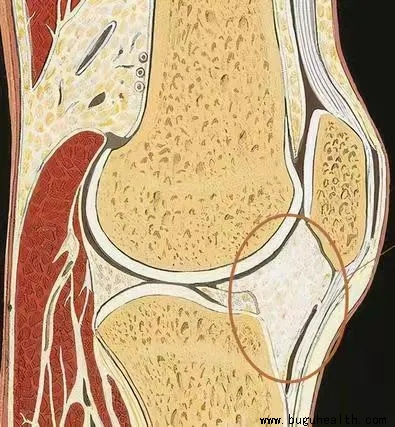

- 布骨医学科普:膝关节疼痛的原因之一,髌下脂肪垫炎 布骨康复医疗中心 ,2021-11-02

- 髌下脂肪垫劳损又称髌下脂肪垫炎、脂肪垫肥厚、Hoffa痛, 是某种因素刺激所造成的急、慢性髌下脂肪垫的无菌性炎症, 可以累及相关的滑膜和肌腱。患者膝关节局部水肿、出血及粘连, 出现膝关节疼痛、活动受限, 严重者膝关节僵直、跛行等, 不同程度影响患者的工作和日常生活。 .....